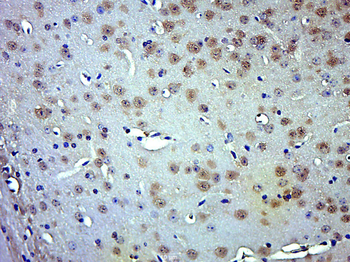

50 μl, 100 μlPhospho-Smad3 (Thr179) Rabbit Polyclonal Antibody [orb313112]

FC, ICC, IF, IHC-Fr, IHC-P

Bovine, Canine, Equine, Porcine, Sheep

Human, Mouse, Rat

Rabbit

Polyclonal

Unconjugated

100 μl, 200 μl, 50 μlSMAD7 Rabbit Polyclonal Antibody [orb500819]